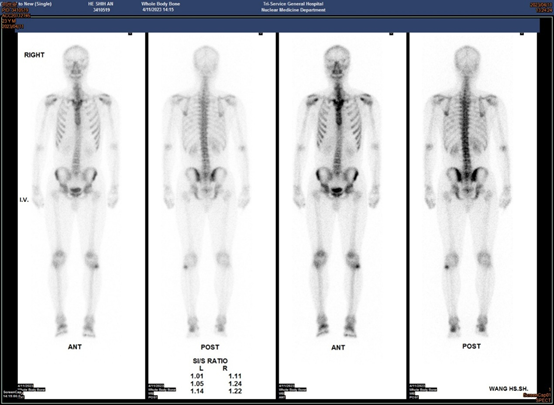

A 23-year-old soldier visit Outpatient Department of Rehabilitation of our hospital for the pain in the bottom of his feet. The patient said that once he exercised the feet hurt a lot, and the pain would relieve after rest. He has been troubled by such a situation since high school. Recently, the situation worsened due to intense training in military service. He mentioned that he had been suffering from chronic knee pain for a long time. The knees were burning and looked reddish, causing pain after exercise even now can be felt heat around knee. During physical examination, we found pustulosis on both palms (Figure 1A & 1B) and hyperostosis in the left sternoclavicular joint. Furthermore, the patient also had a little acne on his face. Plain films of the knee and foot/ankle joints did not show abnormality (Figure 2A). Whole body bone scan (WBBS) divulged a boosted uptake of 99mTc-methylene diphosphonate (99mTc-MDP) at the left knee and both foot/ankle joints (Figure 3). Single photon Emission Computed Tomography (SPECT) with Computed Tomography (CT), using the same tracer, revealed precise pathology at the left knee and both foot/ankle joints (Figure 4A & 4B). The initial impression for this patient was SAPHO syndrome together with enthesopathy of left knee, and both foot/ankle joints. Patient was treated with pain killer and rehabilitation modalities, and his painful episodes improved after three months.

Figure 3 The WBBS of the patient could see the enhancement at the left knee, which very strong uptake indicating the exact location of lesion.

This case report is the only one that confirms the uptake on the SPECT-CT of the knees and feet in a case of SAPHO syndrome. In this case, we noticed the enhancement of the knee and foot confirmed from SPECT-CT images. Based on the skeletal scintigraphy, despite of the enhancement on bilateral the sternoclavicular joints, the involvement of both knees (especially the left side), and both feet/ankle joints (also especially the left one) was confirmed. These kinds of signs in knee and foot/ankle joints are out of features of SAPHO syndrome. As for the SPECT-CT scan, this might be the first case using SPECT/CT to scan the knees and the feet of a person with SAPHO syndrome.2,3,5,6 As shown on the SPECT/CT, hyperostosis appears on the left knee in the axial view and lesions on bilateral knees (left >> right) in the coronal view. For the feet, we can find large area enhancement covering them.